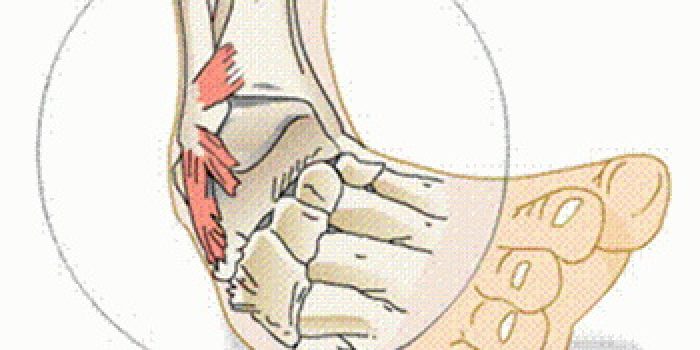

رگ به رگ شدن یا پیچ خوردن یک مفصل در واقع پاره شدن لیگامان یا رباط اطراف آن مفصل است و علت ایجاد آن اینست که مفصل در وضعیتی قرار می گیرد که لیگامان های اطراف آن تحت کشش زیادی قرار می گیرند و به علت این کشش دچار پارگی می شوند. مثال معمول آن رگ به رگ شدن یا پیچ خوردن مفصل مچ پا است.

برای درمان رگ به رگ شدن یک مفصل در صورت درد شدید، پزشک مفصل را بمدت ۳-۲ هفته به توسط یک آتل یا گچ بی حرکت می کند تا درد بیمار کاهش یابد و سپس هرچه زودتر حرکات مفصل را شروع کرده تا دچار محدودیت حرکت نشود. در صورتی که رگ به رگ شدن همراه با درد شدیدی نباشد نشانه آسیب دیدگی کم است. در این مواقع میتوان درمان را با بانداژ ادامه داد بشرط اینکه بیمار بمدت چند هفته فشار زیادی به مفصل آسیب دیده وارد نکند.

اگر درمان رگ به رگ شدن مفصلی به درستی انجام نشود لیگامان ها به درستی ترمیم نیافته و مفصل دچار ناپایداری میشود. این بیماران در آینده دچار رگ به رگ شدن های مکرر می شوند و ممکن است برای درمان این وضعیت اعمال جراحی بازسازی پیچیده مورد نیاز شود. پس عاقلانه است در اولین بار پیچ خوردگی یک مفصل درمان آن به درستی انجام شود.